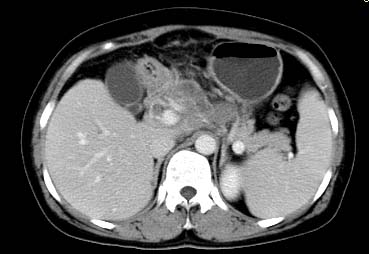

以下是引用西北一只狼在2008-6-30 20:58:00的发言:[br]肝左叶胆管细胞ca并肝门淋巴结转移、胰腺、胃小弯浸润

以下是引用ydx_74在2008-6-30 21:54:00的发言:[br]左叶胆管细胞ca并肝门淋巴结转移、胰腺、胃小弯浸润